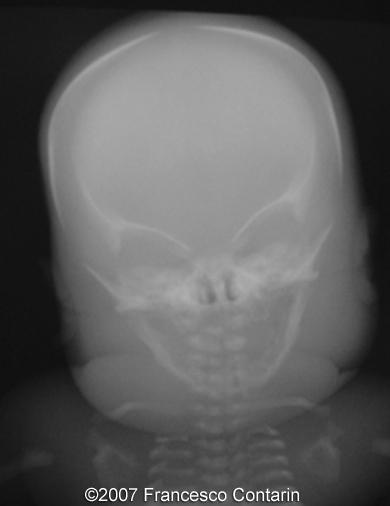

The patient was counseled and decided to terminate the pregnancy. At 30 week of pregnancy, a cesarean section was performed. A female baby was born with the Apgar scores 4 and died after 4 minutes. Post natal X-ray was performed and we find square shape iliac wings and bicycle handle-like clavicles. The karyotype was normal (46 XX) and final diagnosis was: short rib-polydactyly syndrome.

Images 16, 17. Postnatal radiograms - bicycle handle like clavicles (left); and micromelia with dominant rhizomelia (right).

Images 20, 21. Postnatal radiograms - pelvis with square shape iliac wings.